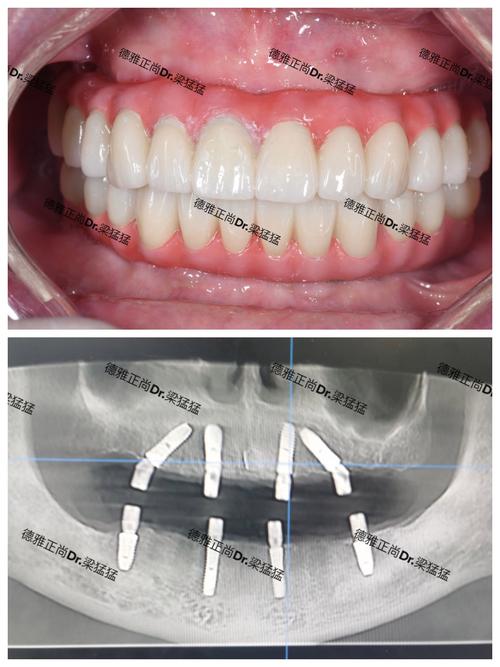

- 技工所根据模型制作最终的高强度、美观的固定牙桥(通常为全瓷或高强度烤瓷)。

- 将最终牙桥通过螺丝或粘接剂固定在种植体基台上。